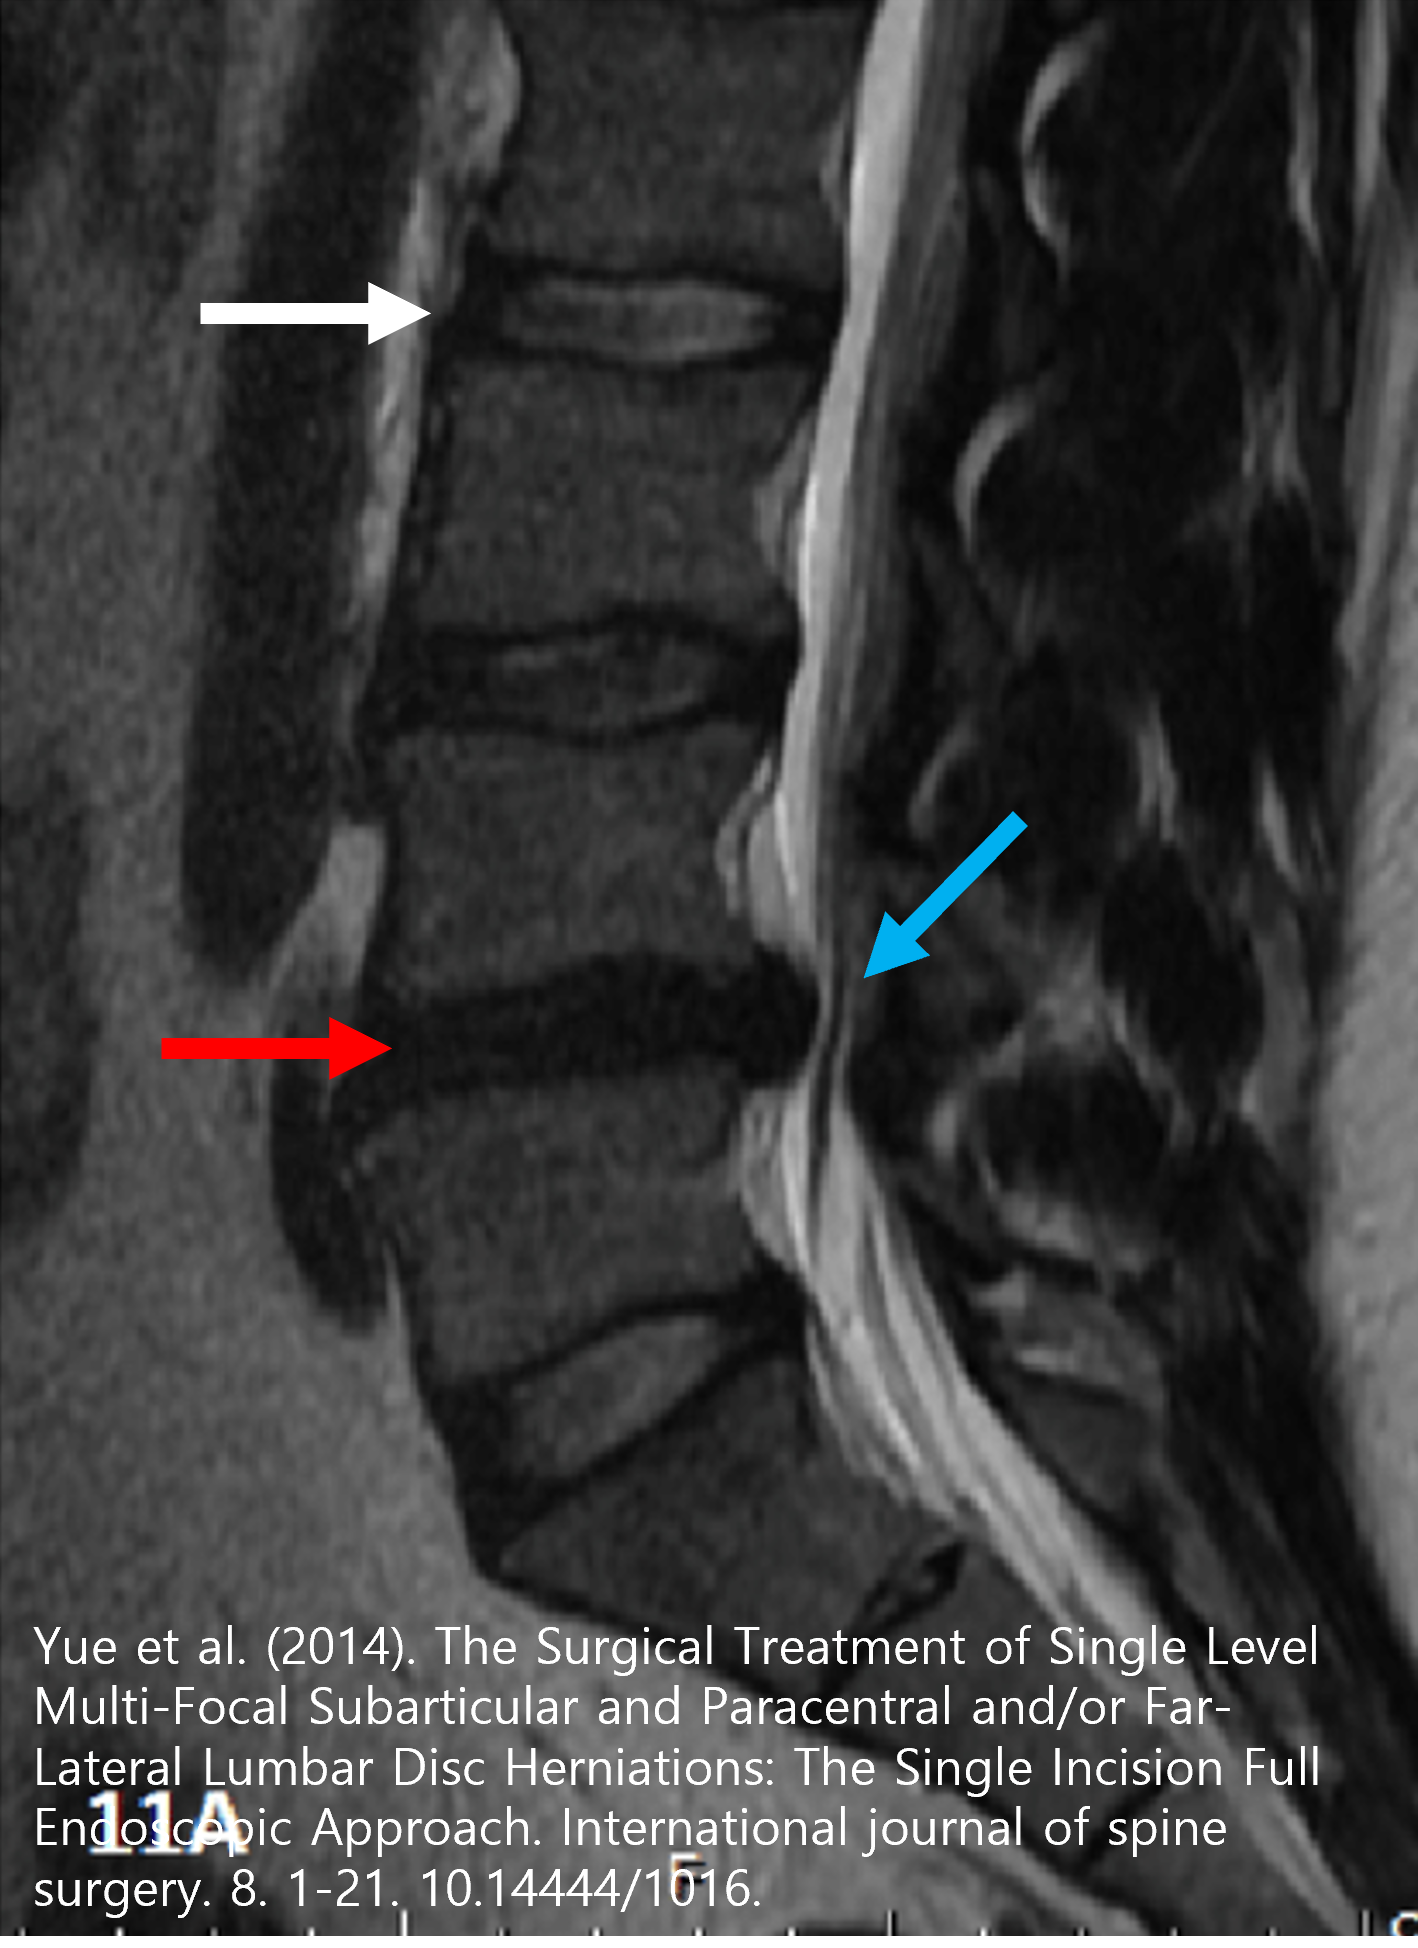

위 MRI 영상을 보시면 정상적인 디스크의 내부는 (하얀 화살표) 수분으로 인한 높은 신호강도를 보여 하얗게 보여야 하지만, 손상된 디스크의 내부는 (붉은 화살표) 수핵이 후방으로 탈출된 후 흡수가 되어 수분이 없어 저신호강도로 검은색으로 보이게 됩니다. 후방으로 탈출된 디스크 조직 (파란 화살표)는 척추체 후방에 위치한 척추신경을 압박하여 신경증상을 일으키게 됩니다.